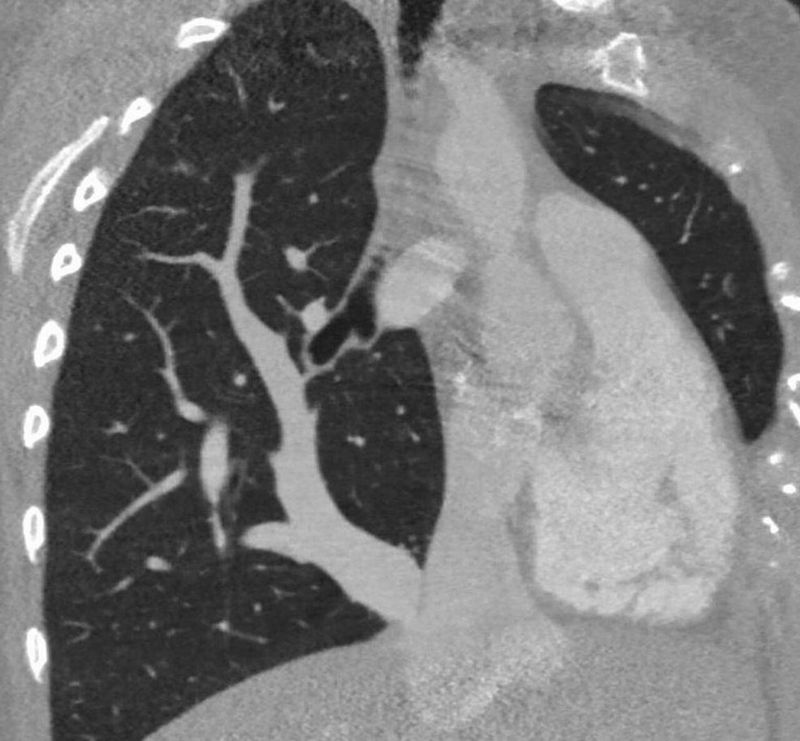

What is your diagnosis

Pneumothorax?

Pneumothorax and the treatment would be a needle thoracotomy.

Tension Pneumothorax?

Pneumothorax